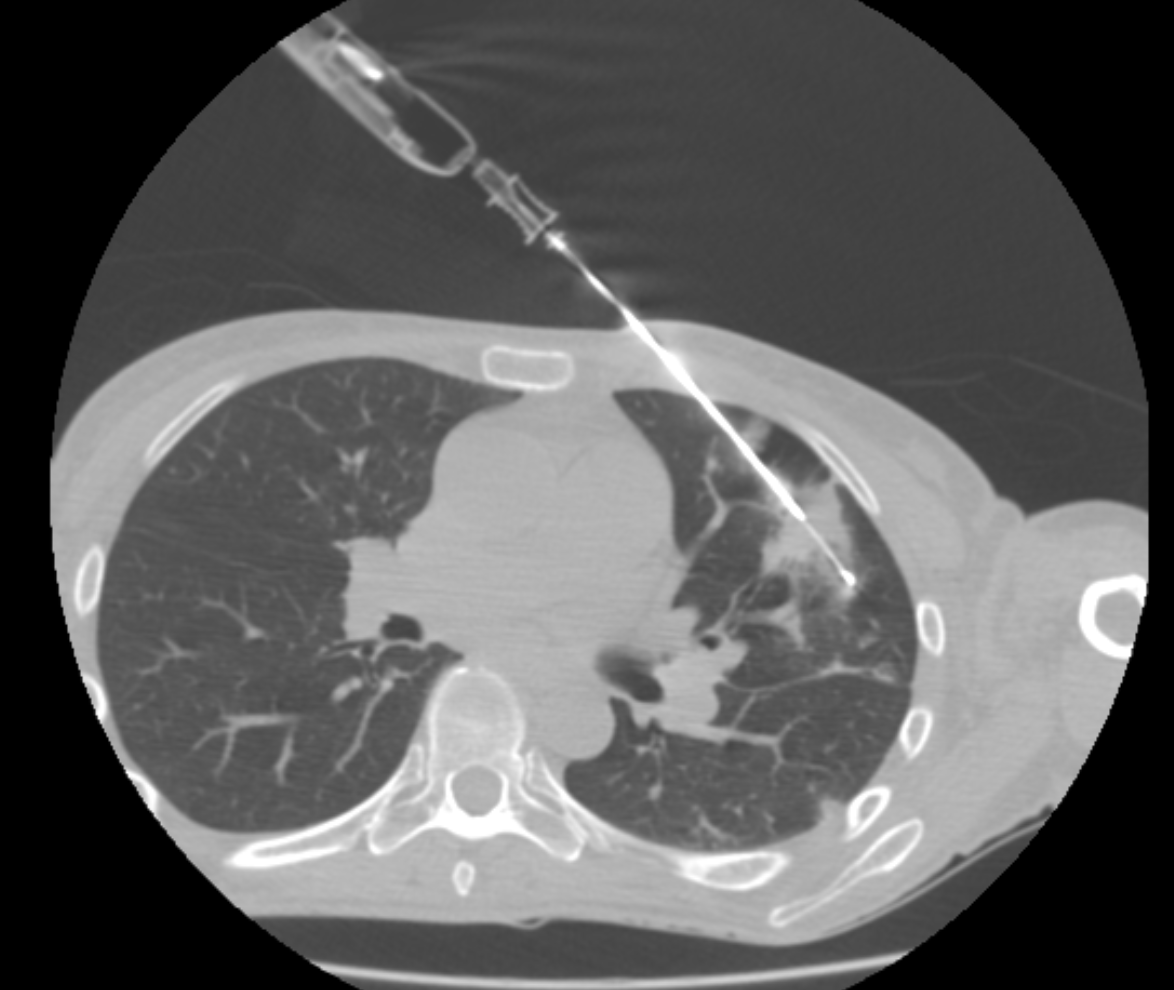

Biopsy

At Spectrum IR, we perform precise, image-guided biopsies across the full spectrum of body tissues—from superficial lymph nodes and thyroid to complex deep organs including bone, liver, kidney, and lung. Using advanced imaging technology, our interventional radiologists target specific tissue with millimeter accuracy, minimising discomfort and recovery time while maximising diagnostic yield. This minimally invasive approach provides your medical team with the critical information needed to determine your optimal treatment path, all while prioritizing your comfort and safety throughout the procedure.